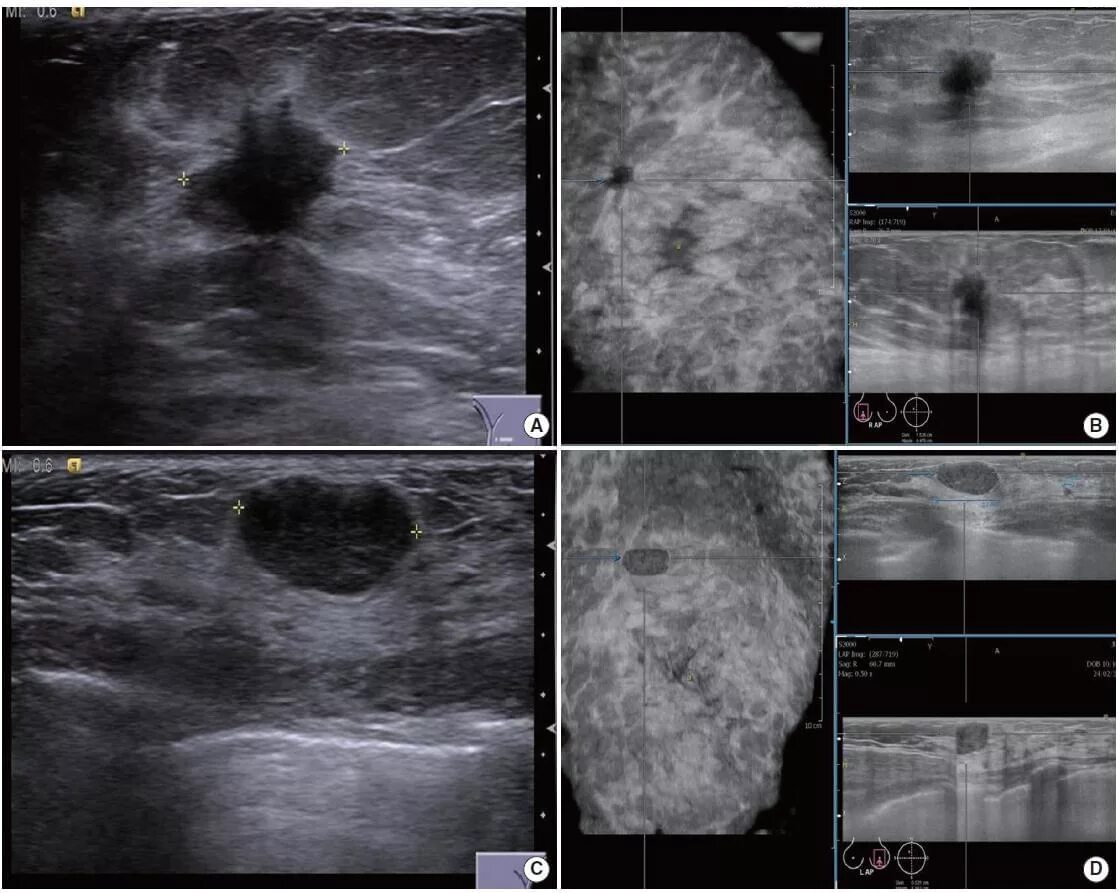

Susp c r